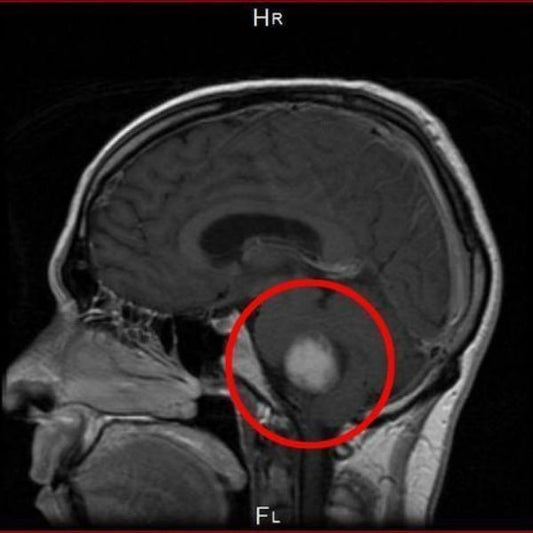

Fifth Court in Italy Ruled Cell Phones Cause Br...

Fifth Court in Italy Ruled Cell Phones Cause Brain Tumors and Determined It Is An Occupational Disease Written by: Martine Vriens, Director of International Legal Affairs for We Are The Evidence On...